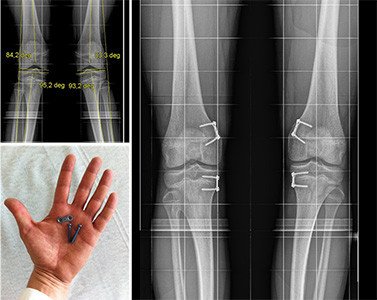

Es besteht eine sehr ungünstige idiopathische Valgusfehlstellung am Kniegelenk auf beiden Seiten. Bei Belassen dieser Fehlstellung droht ein frühzeitiger Verschleiss des Gelenkes aussenseitig.

Nach genauer Analyse der Deformität wird bei noch offenen Fugen ein Plättchen jeweils auf der Innenseite der Ober- und Unterschenkelfuge angebracht, um das Wachstum im Bein entgegen der ungünstigen X-Beinfehlstellung zu steuern.

Das klinische und radiologische Ergebnis zeigt korrekte Achsenverhältnisse. Das Bein ist deutlich besser belastbar und das Risiko eines frühzeitigen Gelenkverschleisses ist minimiert.